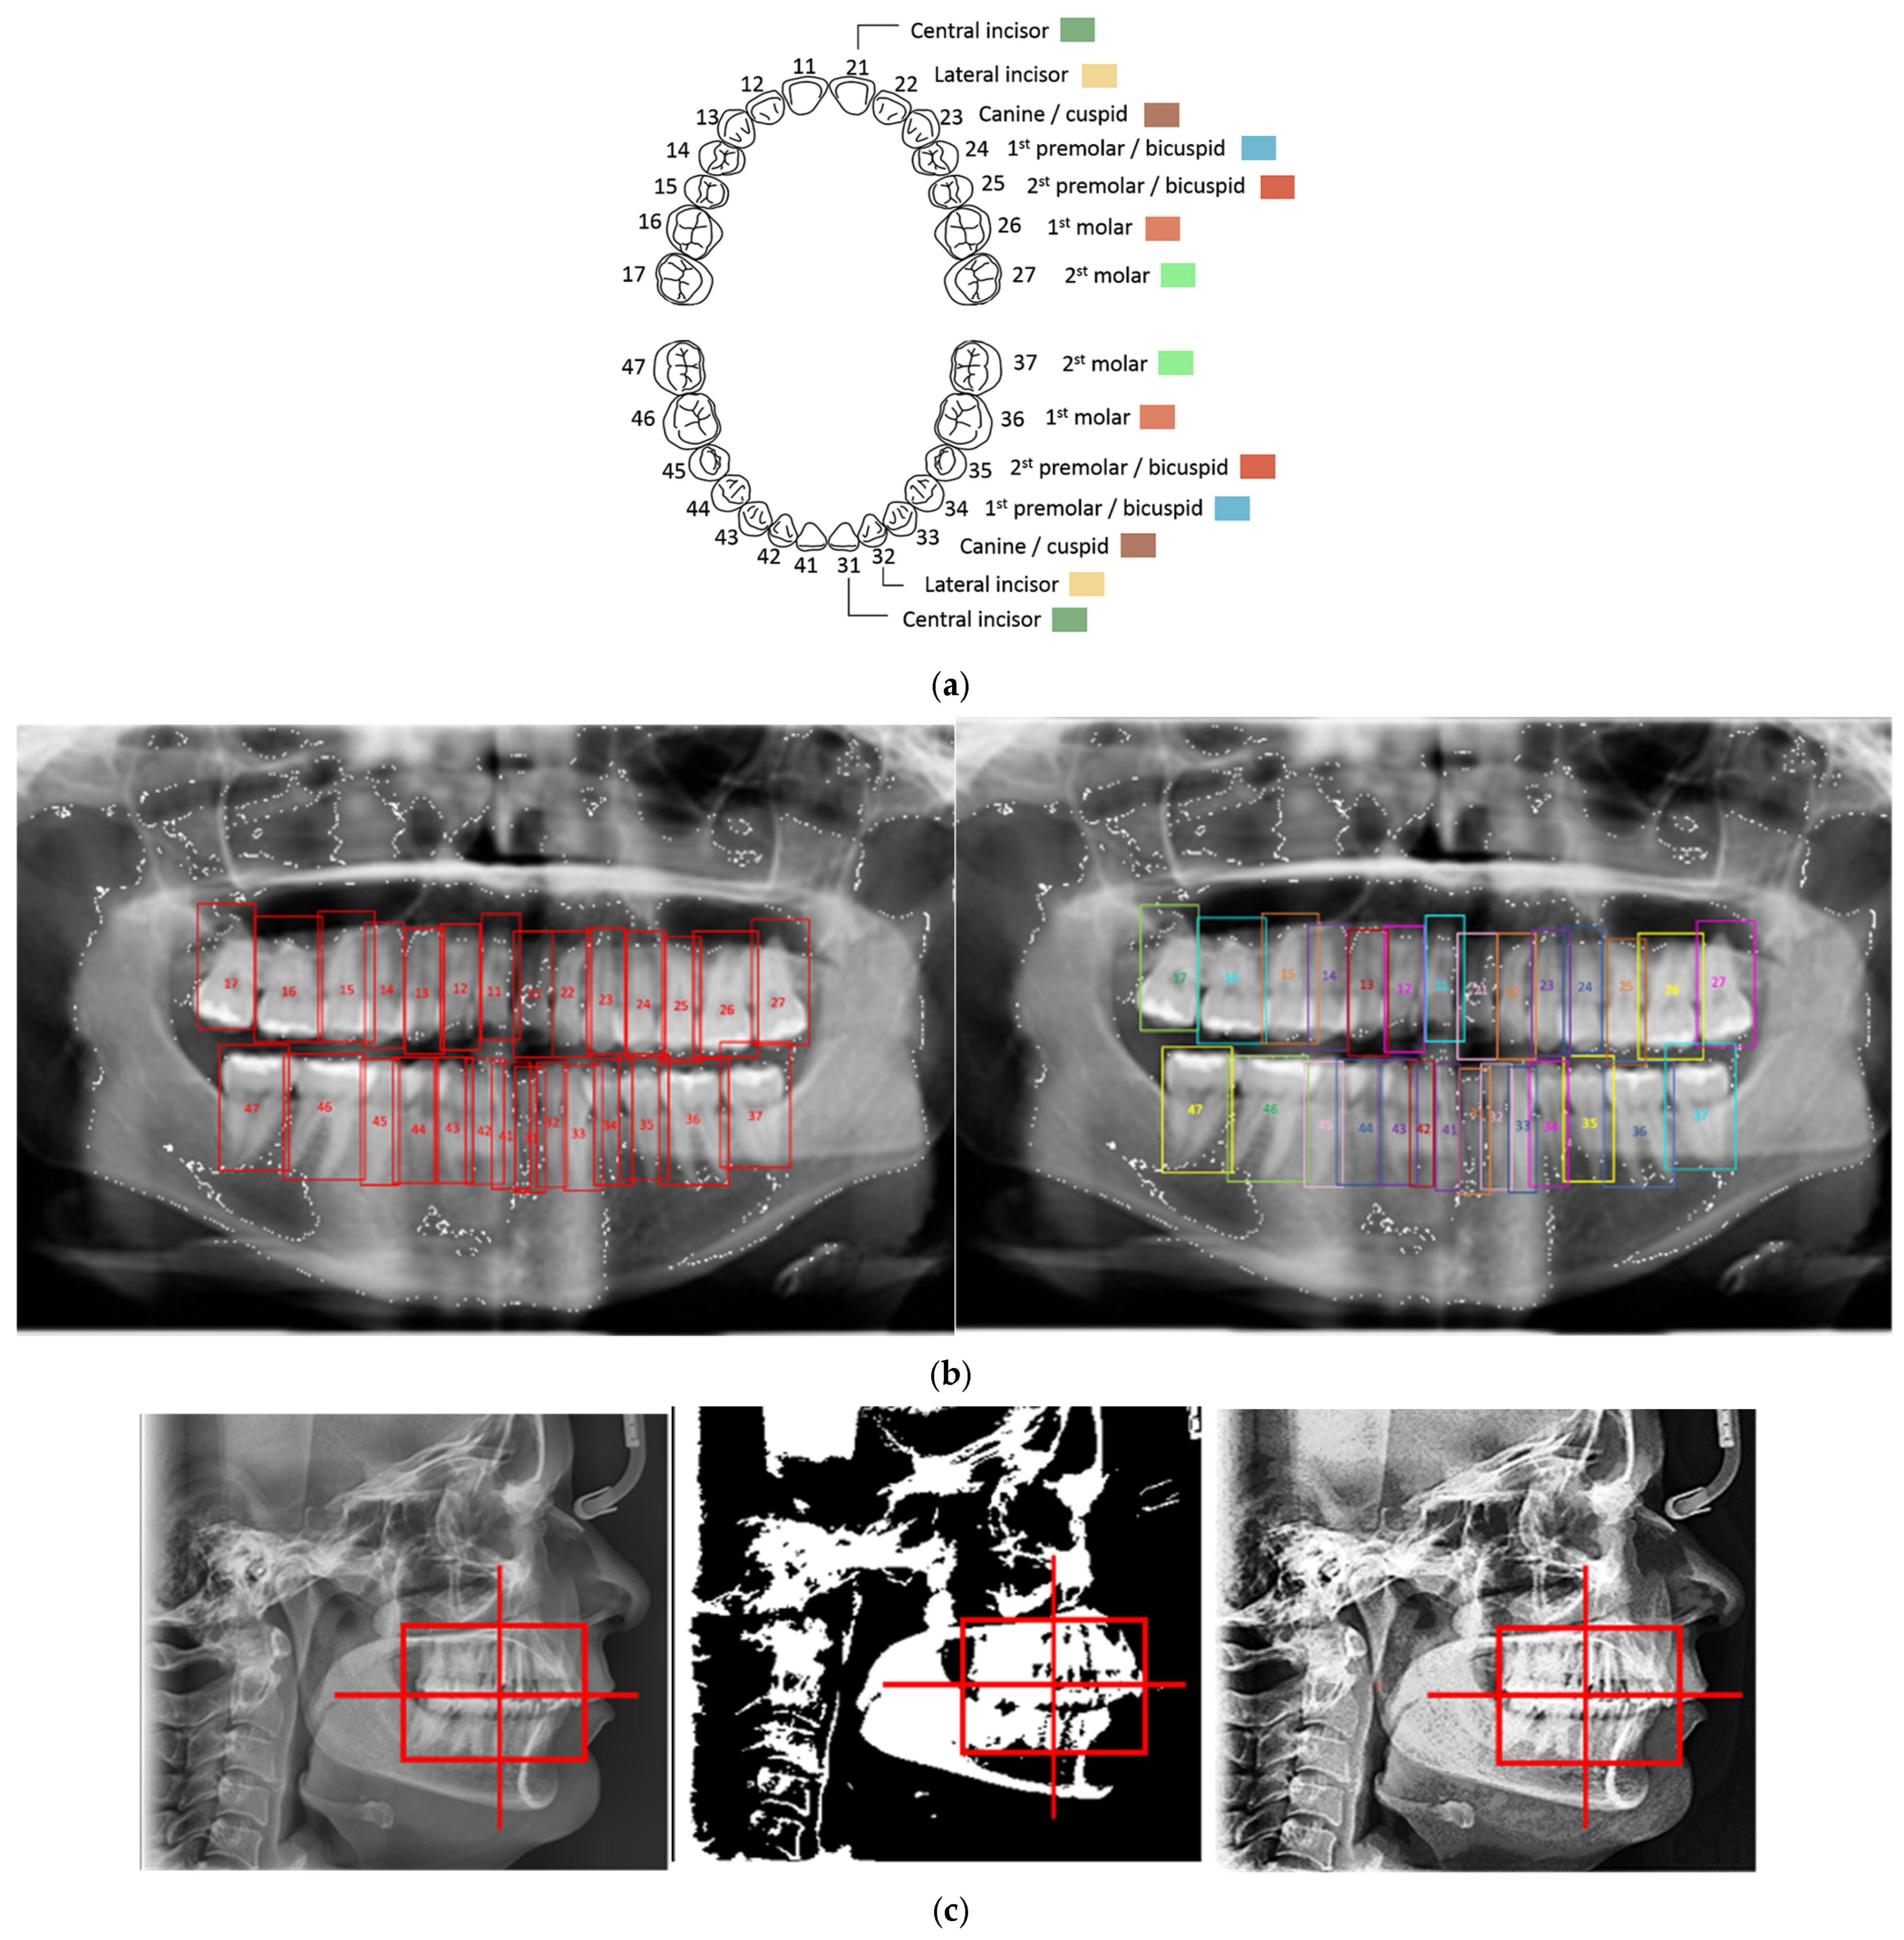

2.2. ROI Handcrafted Feature Detection

2.3. ROI Identification, YOLO-UNet-Based